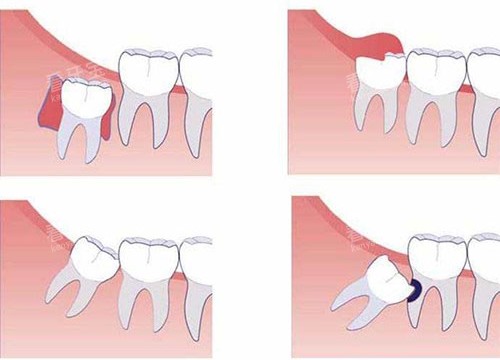

智齿冠周炎:较常见的“肿痛元凶”

如果是年轻人,尤其是18-30岁之间,后槽牙后面的牙龈肿痛大概率是智齿冠周炎。智齿长不出来,牙冠周围的牙龈形成一个盲袋,食物残渣进去就会滋生细菌,引发炎症。

症状:智齿周围牙龈红肿、疼痛,张嘴受限,重度的时候脸会肿,甚至发烧、淋巴结肿大。

处理方法:

- 急性期先做局部冲洗,牙医会用双氧水和生理盐水反复冲洗盲袋,把里面的脏东西冲出来,再上药降低炎症。

- 等炎症消了之后,拍个牙片看看智齿的位置,如果智齿长歪了、反复发炎,建议拔掉。现在拔智齿大多是小切口操作,创伤小,修养时间短,不用太害怕。